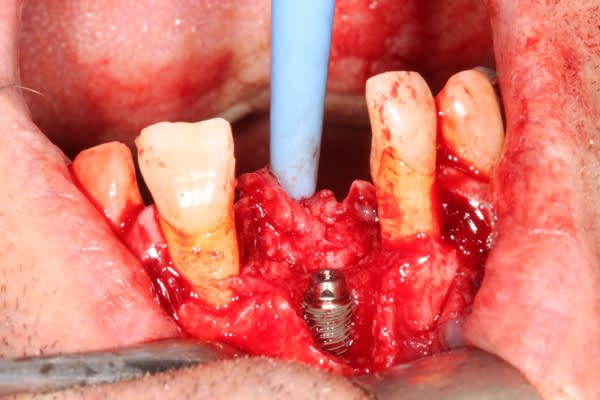

Extraction implantation immédiate mais il y a au moins 7 spires à nue... (photo 1, 2)

dans cette technique un pilier de 2mm de haut est vissé sur l'implant, ce pilier contient un orifice qui permet de transfixer la barre (photo 3,4)

l'espace créé est rempli avec un biomat et le tout est recouvert d'une membrane